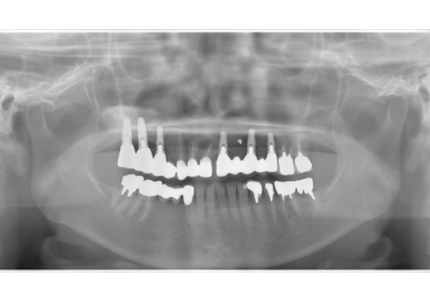

1.初診時口腔内(2007年6月30日)

↑ 2007年6月30日(初診)